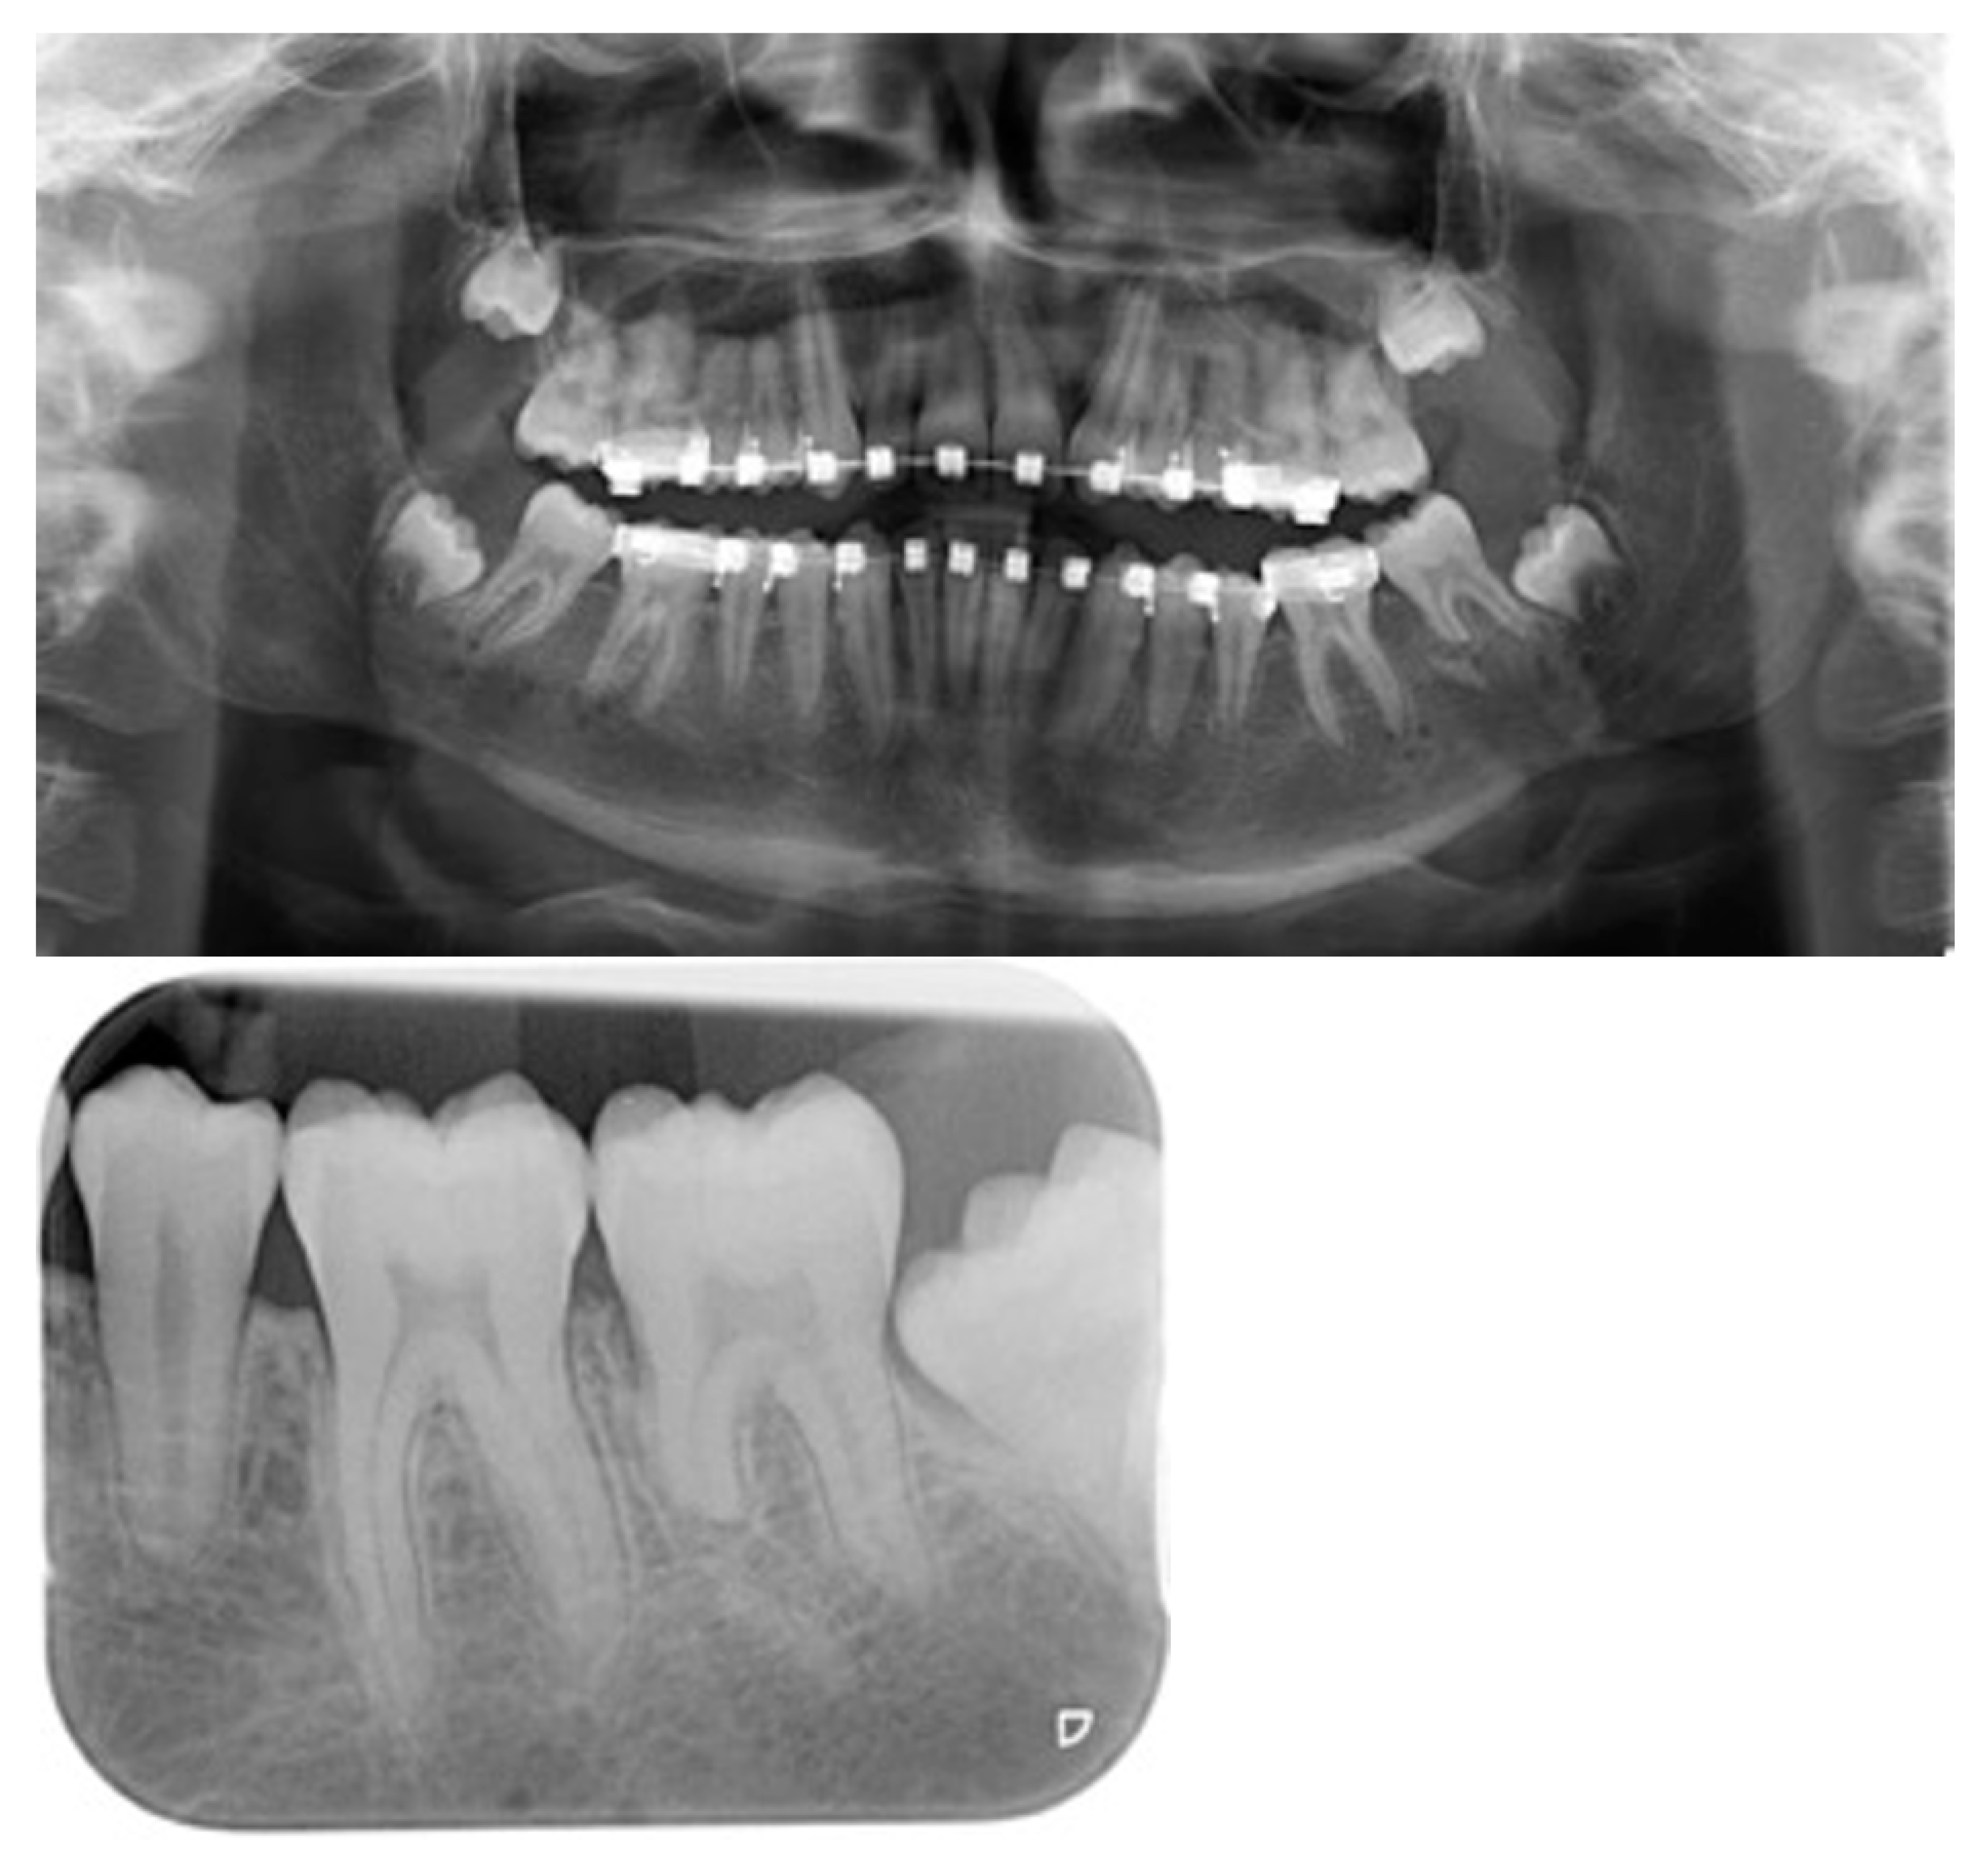

Cone-beam computed tomography (CBCT) was used for the diagnostic workup and the planning of the operation. The Nemotec® program (Biotech, Madrid, Spain) was used for digital preoperative planning (Figure 1). Postoperatively, subjects were evaluated with conventional radiology or CBCT immediately after surgery and at the end of the distraction treatment.

Figure 1.

Cephalometric analysis before Intermolar mandibular distraction osteogenesis (IMDO) treatment. (a) Class II/1 occlusion. (b) Desired mandibular advancement distal to the first mandibular molar.